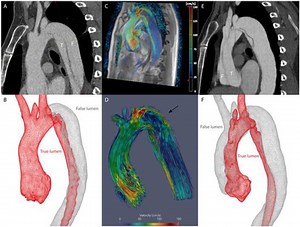

- 4D Flow MRI

Sippin Aorta - 4 D

Lines Aorta - 4D

Aorta - 4D

4D Flow MRI - Evolut Aortic